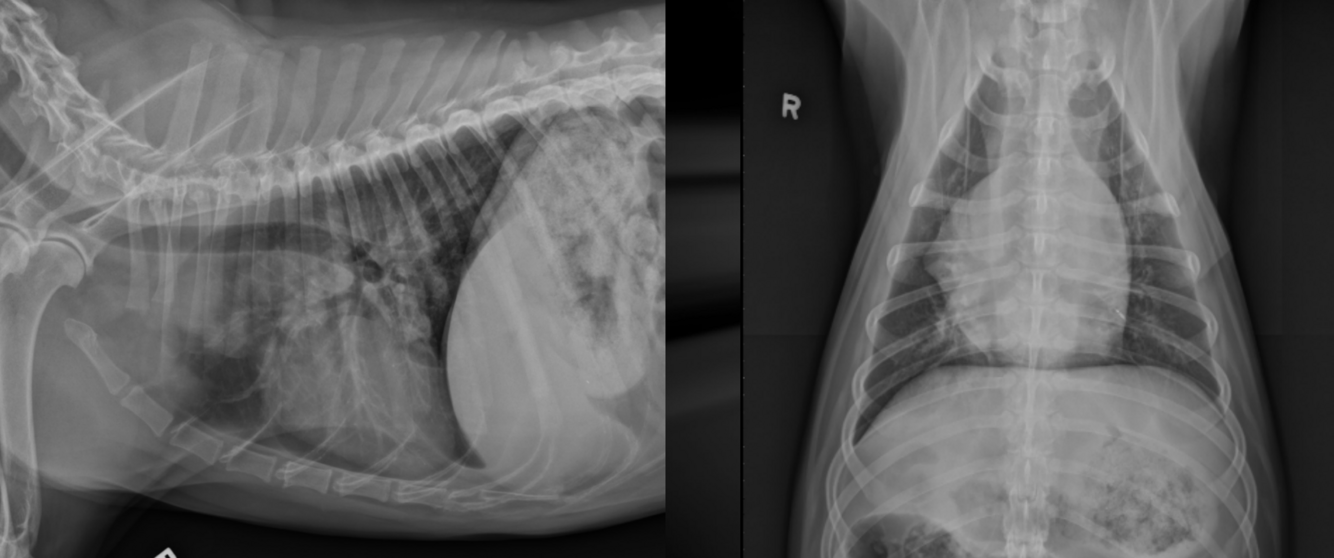

What is shown in this image?

A